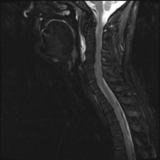

The severe cervical spine pain prompted an emergency MRI examination, which showed a clear prevertebral inflammatory soft tissue process. On close inspection, a calcific deposit anterior to the dens axis can already be suspected on MRI (especially T2 or axial T1fs Gd+). The calcium depot is only shown very fluffy on X-ray and CT, suggesting an acute stage with precipitation/resorption of the calcific milk.

The longus colli muscle is a less common location of this condition, which should be referred to as HADD or acute calcific deposit. Also affected may be supraspinatus tendon and other tendons of the rotator cuff, extensor carpi radialis tendon, deltoid muscle, or hip adductors.